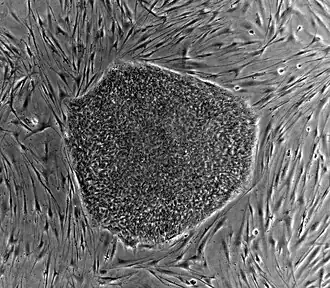

Nearly all research to date has made use of mouse embryonic stem cells (mES) or human embryonic stem cells (hES) derived from the early inner cell mass. Both have the essential stem cell characteristics, yet they require very different environments in order to maintain an undifferentiated state. Mouse ES cells are grown on a layer of gelatin as an extracellular matrix (for support) and require the presence of leukemia inhibitory factor (LIF) in serum media. A drug cocktail containing inhibitors to GSK3B and the MAPK/ERK pathway, called 2i, has also been shown to maintain pluripotency in stem cell culture.[25] Human ESCs are grown on a feeder layer of mouse embryonic fibroblasts and require the presence of basic fibroblast growth factor (bFGF or FGF-2).[26] Without optimal culture conditions or genetic manipulation,[27] embryonic stem cells will rapidly differentiate.

Human embryonic stem cell colony on mouse embryonic fibroblast feeder layer